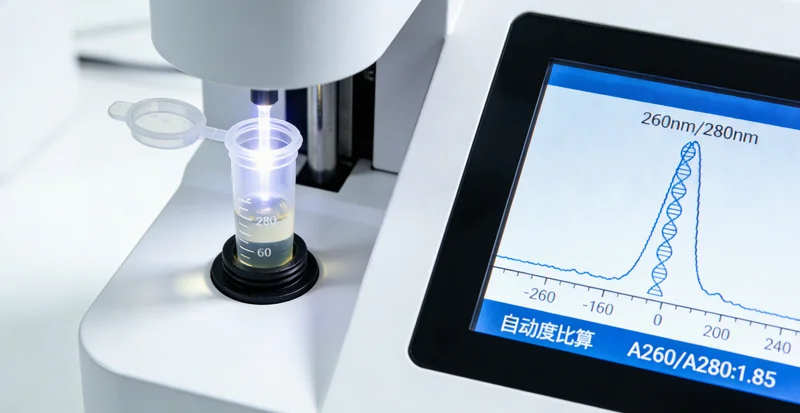

第二,看检测范围和报告内容。Noonan综合征相关的基因不止一个,最常见的是PTPN11,但还有其他如SOS1、RAF1、KRAS等十多个基因。一份负责任的检测报告,不应该只查一个基因,而应该是一个包含核心及相关基因的基因Panel(组合)。报告里除了给出“发现/未发现致病突变”的结果,更重要的是要有专业的临床解读,说明这个突变意味着什么,对治疗和家庭成员的生育有什么指导意义。干巴巴的基因数据,对非专业人士来说,等于没看。